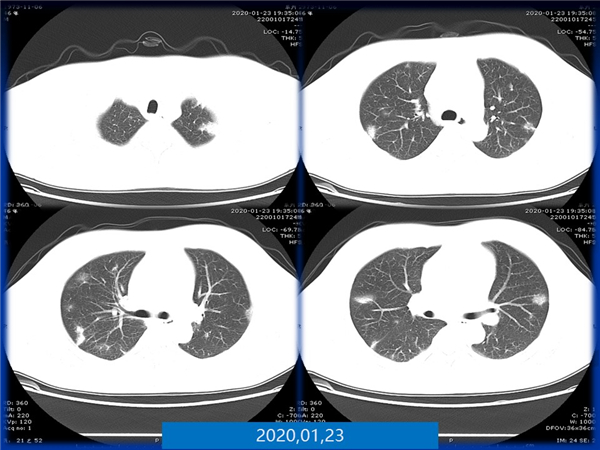

【病例分享】新型冠狀病毒感染肺部CT影像4例(常德市第一人民醫(yī)院)